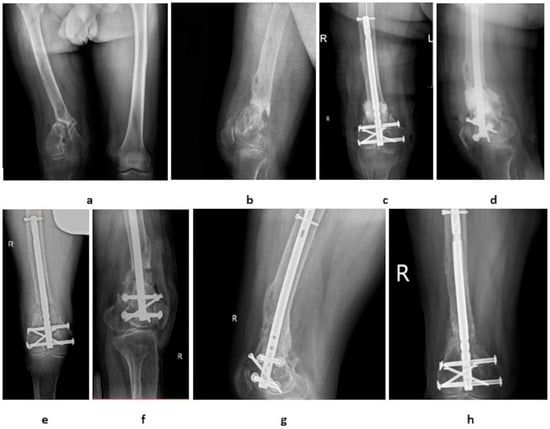

3. Results